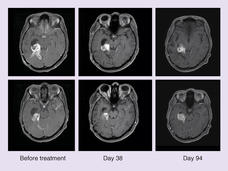

For Some Kids with Brain Cancer, Targeted Therapy Is Better than Chemo

The combination of dabrafenib (Tafinlar) and trametinib (Mekinist) shrank more brain tumors, kept the tumors at bay for longer, and caused fewer side effects than chemotherapy, trial results showed. The children all had glioma with a BRAF V600 mutation that could not be surgically removed or came back after surgery.